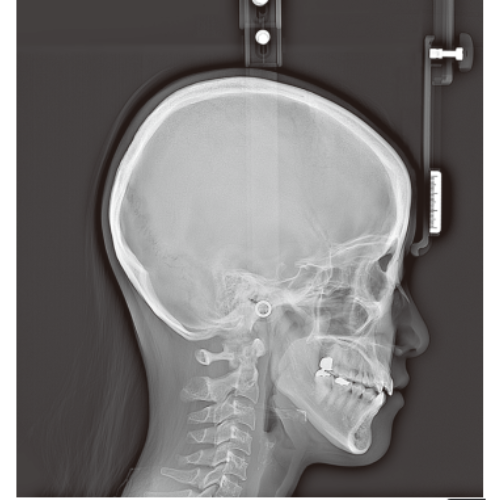

Rayscan Alpha brings another innovative technology with less Recon time and bigger FOV Size. And there are also new features – Fast scan mode, Object scan and Multi FOV.

- Panoramic

- Cephalometric